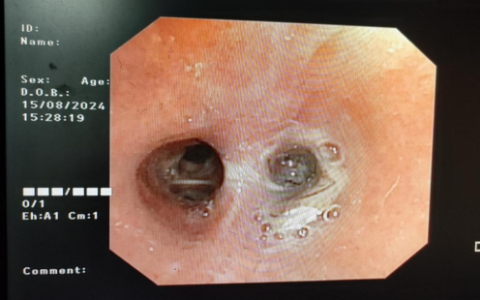

与家属充分沟通后,11月4日,医护人员提前进行病房消毒及各种物品准备,在陈文教授指导下,由两位副主任医师林蓉宇和吴奇鲜共同配合,在病床旁为患者实施腹膜透析置管术。

林蓉宇介绍,当时手术过程也是惊险万分,患者气促躺不平为手术增加了难度,加上患者的心功能很差,稍有不慎刺激到患者,容易诱发急性心率衰竭。好在有惊无险,整个手术过程很顺利,术中试水引流顺畅,术后常规腹膜透析,患者转危为安。